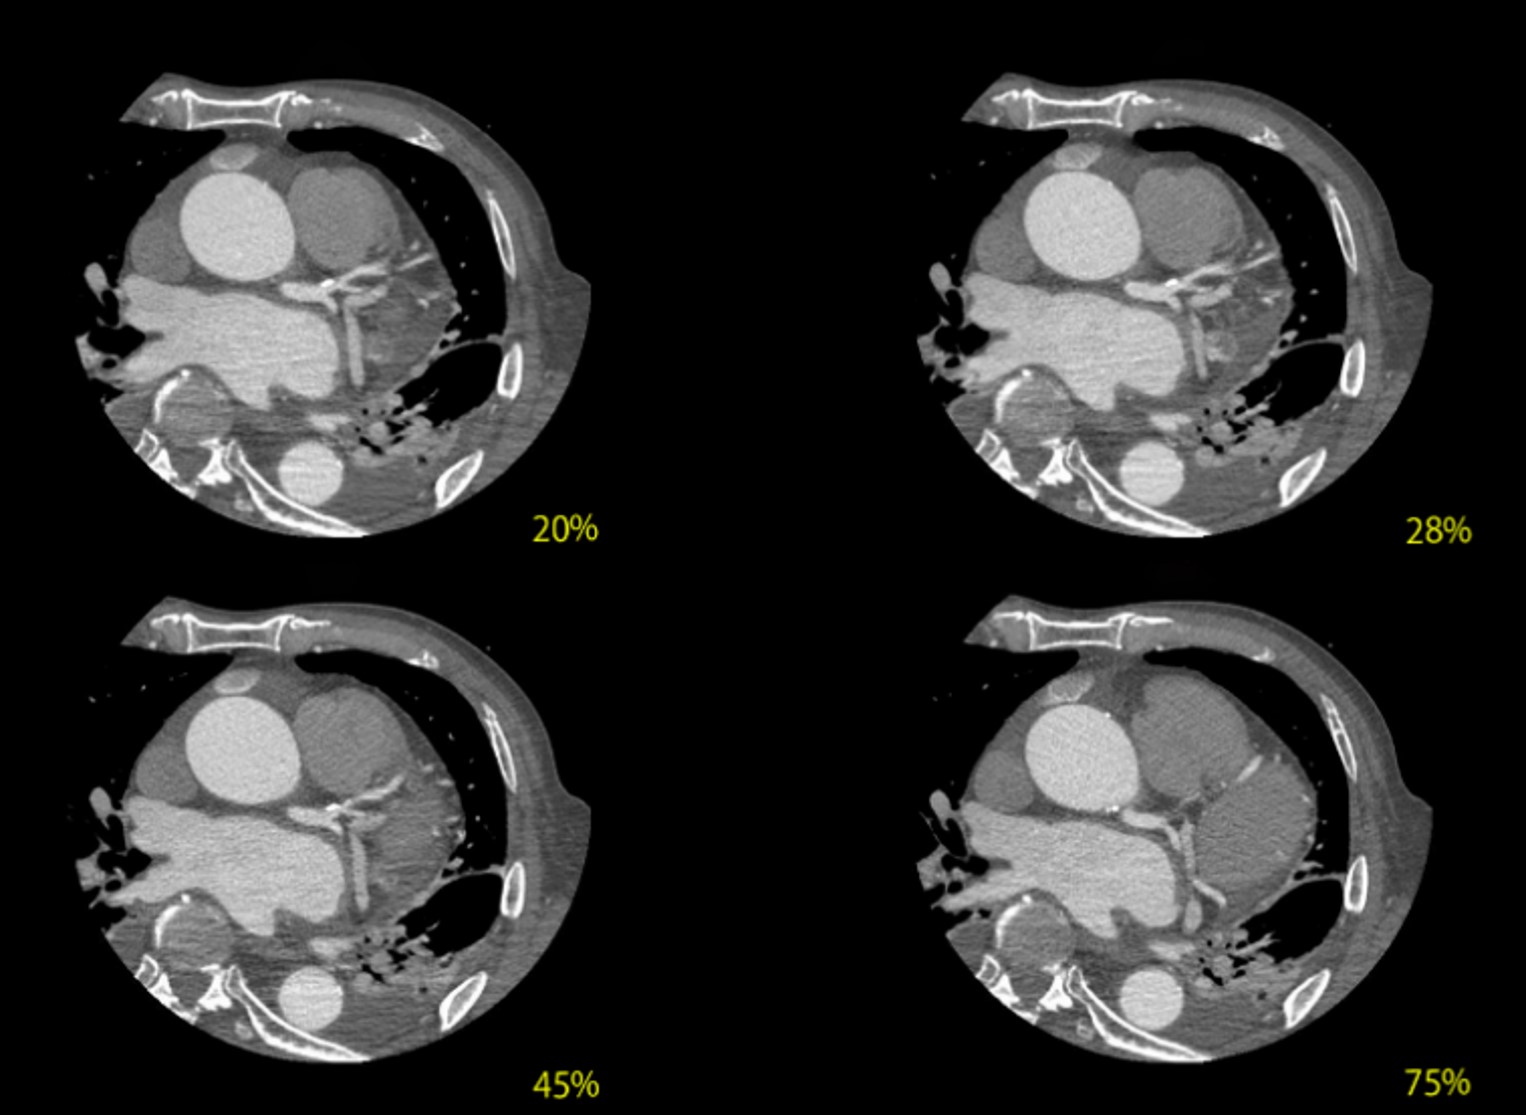

またHR60において、冠動脈は拡張中期である75%付近でモーションの影響が少ないですが、画像のように、どのフェーズでSSF2.0の画像を作成しても冠動脈の評価が可能な画像を提供することができます。

RevolutionCT_Kinki05.jpg

図4 SSF2.0を用いた各心位相でのAxial画像